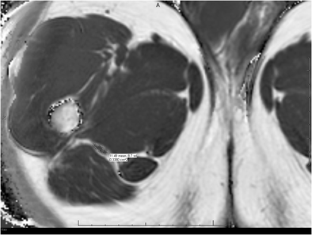

Zoomed images showing the fat fraction measurements. Zoomed image showing the sciatic nerves and their measurements at level A (figure A and B) and level B (figure C and D). (GIF 6 kb)

63-year-old with right buttock pain and sciatica for two years, suspected piriformis syndrome. Axial T2 SPAIR (A) image shows asymmetrically hyperintense right sciatic nerve, even better identified on diffusion image (B). On mDixon quant image (C), notice increased fat fraction of the right sciatic nerve vs left (31.5% vs 27.6%) as well as increased nerve area (0.27 vs 0.25cm2). (GIF 6 kb)